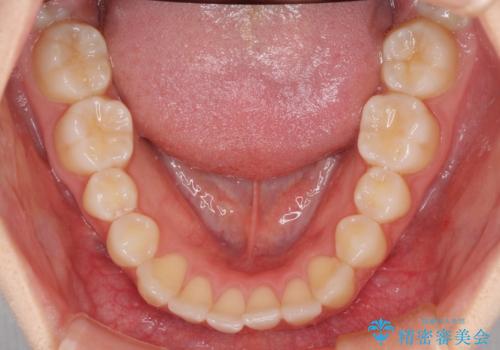

前歯のクロスバイト インビザラインによる矯正治療

- 前歯のクロスバイトを気にして来院された患者様です。

短期間での治療を希望され、ワイヤー装置とインビザラインとで悩んでいましたが、自己管理を徹底すると言うことでインビザラインによる矯正治療を行うこととしました。

しっかりとインビザラインの装着時間を守っていただいたので、1年弱で矯正治療を終えることができました。